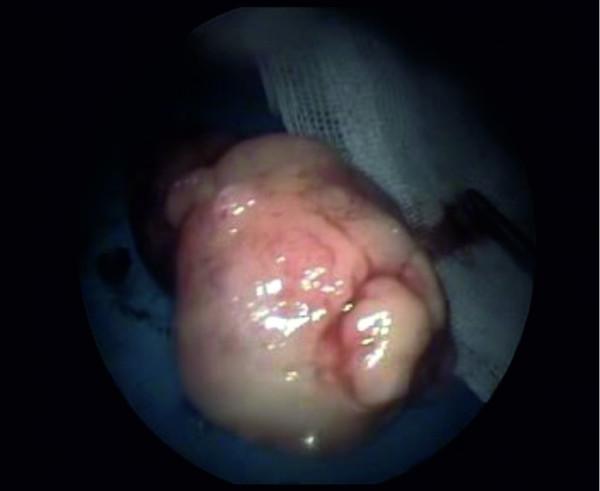

A 27-year-old Caucasian man complaining of a nasal obstruction was admitted to our clinic in January 2006. A transnasal endoscopic examination revealed a mass arising from the nasal septum which was completely removed using an endoscopic approach. Histologically, it was determined to be a benign teratoma.

一名27岁的白人男性因鼻塞于2006年1月入住我院。经鼻内镜检查发现鼻中隔有一肿块,采用内镜方法将其完全切除。组织学检查确定为良性畸胎瘤。